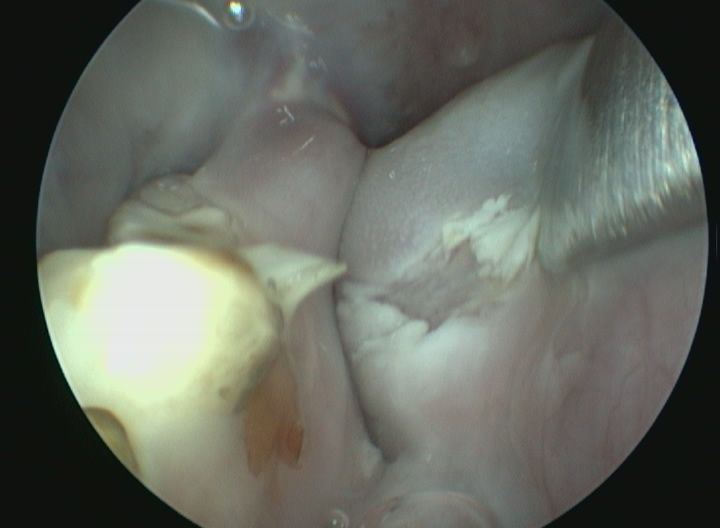

Pour prévenir cette maladie, seule la consommation de foin (foin de Crau ou de phléoles) ou d'herbe fraîche permet l'usure efficace des molaires. Les signes de malocclusion sont des signes de salivation, de refus de s'alimenter, de l'amaigrissement et l'apparition de sécrétions oculaires. En cas d'infection, on observera l'apparition d'abcès dentaires. Le traitement fait appel à la taille des dents sous anesthésie (appelée parage dentaire) par un vétérinaire spécialisé. Cette taille de dent est, si possible, réalisée à l'aide d'une caméra endoscopique pour examiner les dents localisées dans le fond de la cavité buccale et évaluer des lésions plus discrètes.

Pour déterminer l'origine et les caractéristiques de l'abcès, l'idéal est de réaliser un examen d'imagerie précis comme le scanner. Le scanner correspond à un examen radiographique en trois dimensions. Le traitement de choix est typiquement chirurgical et médical. Certaines de ces chirurgies peuvent être particulièrement complexes et nécessiter l'utilisation d'un endoscope.